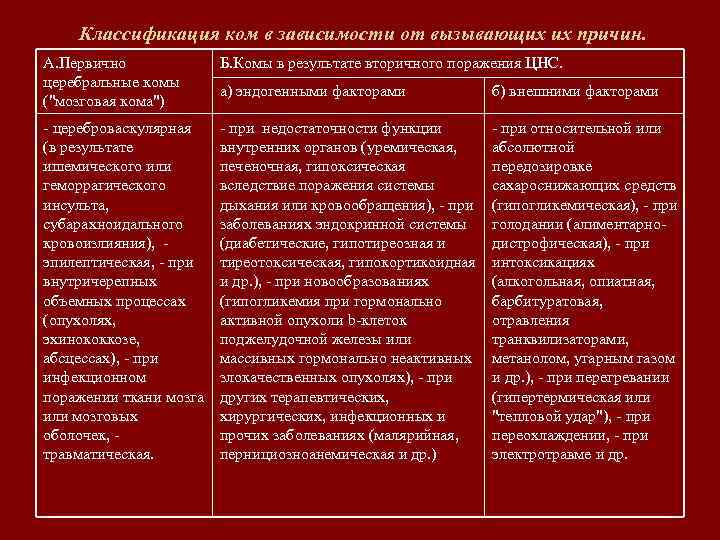

Классификация ком в зависимости от вызывающих их причин. А. Первично церебральные комы ("мозговая кома") Б. Комы в результате вторичного поражения ЦНС. а) эндогенными факторами б) внешними факторами - цереброваскулярная (в результате ишемического или геморрагического инсульта, субарахноидального кровоизлияния), эпилептическая, - при внутричерепных объемных процессах (опухолях, эхинококкозе, абсцессах), - при инфекционном поражении ткани мозга или мозговых оболочек, травматическая. - при недостаточности функции внутренних органов (уремическая, печеночная, гипоксическая вследствие поражения системы дыхания или кровообращения), - при заболеваниях эндокринной системы (диабетические, гипотиреозная и тиреотоксическая, гипокортикоидная и др. ), - при новообразованиях (гипогликемия при гормонально активной опухоли b-клеток поджелудочной железы или массивных гормонально неактивных злокачественных опухолях), - при других терапевтических, хирургических, инфекционных и прочих заболеваниях (малярийная, пернициозноанемическая и др. ) - при относительной или абсолютной передозировке сахароснижающих средств (гипогликемическая), - при голодании (алиментарнодистрофическая), - при интоксикациях (алкогольная, опиатная, барбитуратовая, отравления транквилизаторами, метанолом, угарным газом и др. ), - при перегревании (гипертермическая или "тепловой удар"), - при переохлаждении, - при электротравме и др.

Классификация ком в зависимости от вызывающих их причин. А. Первично церебральные комы ("мозговая кома") Б. Комы в результате вторичного поражения ЦНС. а) эндогенными факторами б) внешними факторами - цереброваскулярная (в результате ишемического или геморрагического инсульта, субарахноидального кровоизлияния), эпилептическая, - при внутричерепных объемных процессах (опухолях, эхинококкозе, абсцессах), - при инфекционном поражении ткани мозга или мозговых оболочек, травматическая. - при недостаточности функции внутренних органов (уремическая, печеночная, гипоксическая вследствие поражения системы дыхания или кровообращения), - при заболеваниях эндокринной системы (диабетические, гипотиреозная и тиреотоксическая, гипокортикоидная и др. ), - при новообразованиях (гипогликемия при гормонально активной опухоли b-клеток поджелудочной железы или массивных гормонально неактивных злокачественных опухолях), - при других терапевтических, хирургических, инфекционных и прочих заболеваниях (малярийная, пернициозноанемическая и др. ) - при относительной или абсолютной передозировке сахароснижающих средств (гипогликемическая), - при голодании (алиментарнодистрофическая), - при интоксикациях (алкогольная, опиатная, барбитуратовая, отравления транквилизаторами, метанолом, угарным газом и др. ), - при перегревании (гипертермическая или "тепловой удар"), - при переохлаждении, - при электротравме и др.